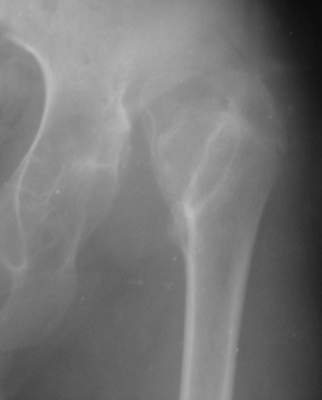

"Поздний" (14 лет) врожденный вывих (подвздошный) бедра |

Dear collegues,Мальчик, 14 лет. Из Узбекистана...Никакой документации на данный момент нет, но со слов выяснилась приблизительно следующая картина... Патологию диагностировали в 2 года...якобы она была двусторонней (скорее всего дисплазия справа и вывих слева),лечили то ли функционально то ли закрытым вправлением под наркозом...как бы то ни было около года гипсовался в различных позах по-Лоренцу...Потом вроде бы повязка сломалсь (слева) и родителям сообщили о рецидиве вывиха...С тех пор (с 3 лет) никак не лечился...С возрастом стало возникать укорочение левой н. конечности, что особенно то и не беспокоило как выяснилось...2 года назад (12 лет) появились боли в левом тазобедренном суставе (на стороневыцвиха)...Вот это то (боли) и являются главной причиной обращения в данное время (14 лет).Укорочение левой н. конечности на 5 см не воспринимается как главная проблема...Снимки в приложении.Что делать?